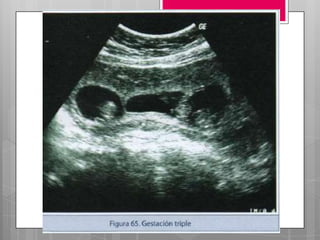

GESTACION MULTIPLE

 INCIDENCIA

 USA 3%. 1 de c/90 embarazos, > en mujeres

negras que en blancas.

 El índice esta > como consecuencia del >

de la edad materna y el uso + fx de las

tecnologías de reproducción asistida (TRA)

y los fármacos inductores de la ovulación.

GESTACION MULTIPLE  INCIDENCIA USA 3%. 1 de c/90 embarazos, > en mujeres negras que en blancas.  El índice esta > como consecuencia del > de la edad materna y el uso + fx de las tecnologías de reproducción asistida (TRA) y los fármacos inductores de la ovulación.